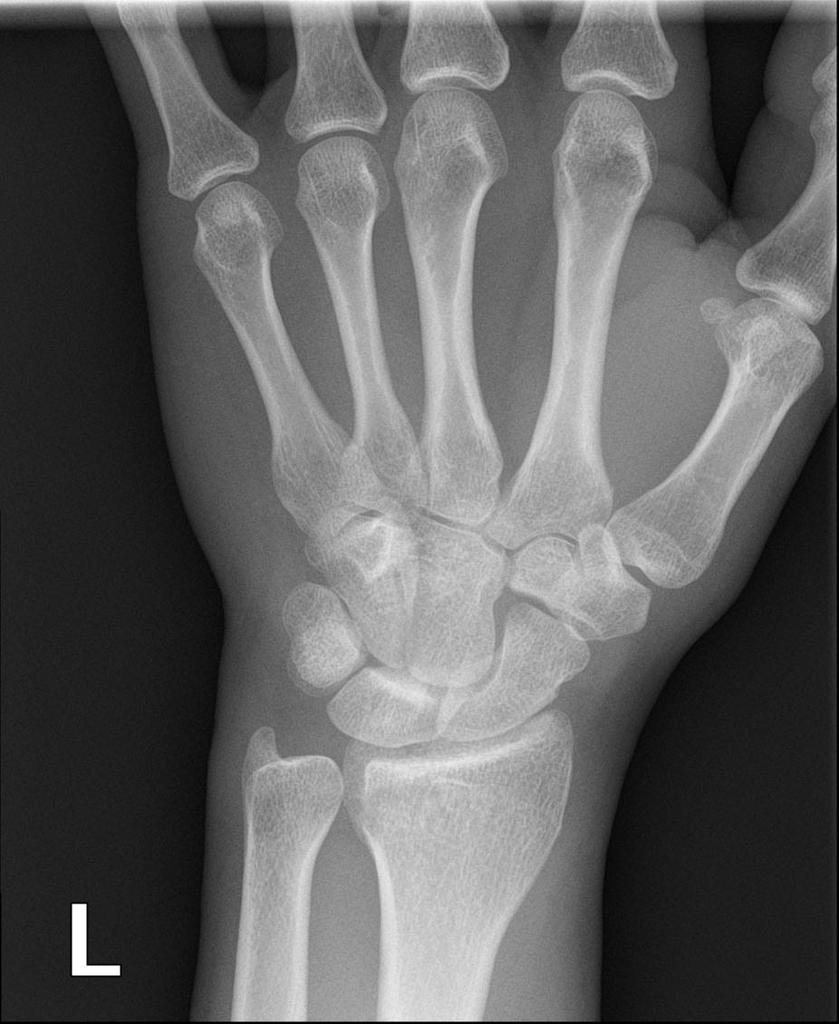

Az eset egy 67 éves nő volt, akinél intraartikuláris instabil distalis radius törést diagnosztizáltak jobb oldali dorsalis medialis töréssel (1A-E ábra). Nincs dohányzás, cukorbetegség vagy alkoholfogyasztás. Sétáló nélkül is tud járni.

1. ábra A preoperatív képalkotás a distalis radius intraartikuláris törését mutatta.

A és B: Preoperatív röntgen,